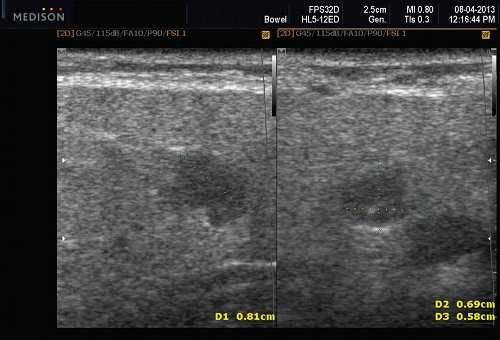

- обструктивные сиаладениты, развивающиеся при затруднении оттока слюны при обструкции выводного протока камнем (рис. 5-7) или сгустившимся секретом, а также вследствие рубцового стеноза протока. По распространенности процесса различают очаговый, диффузный сиаладениты и сиалодохит - воспаление выводного протока. Течение процесса может быть острым и хроническим;

Рис. 5. Камень протока поднижнечелюстной слюнной железы.

Рис. 6. Камень в паренхиме поднижнечелюстной слюнной железы.

Рис. 7. Камень в протоке поднижнечелюстной слюнной железы.